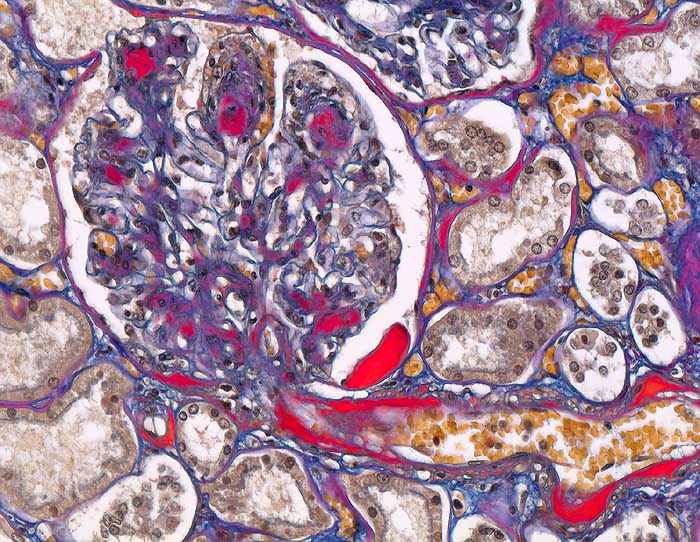

PathoPic ID 6180 - Diabetische noduläre Glomerulosklerose Kimmelstiel-Wilson

Diabetische noduläre Glomerulosklerose Kimmelstiel-Wilson

Systemerkrankung/Immunpathologie

Niere

Niere, Harnwege

Arteriolosklerose von Vas afferens und efferens. Noduläre Mesangiumverbreiterung. Kapseltropfen im Bowman'schen Kapselraum.

Diabetes mellitus Typ II seit 20 Jahren.

Histologie

200